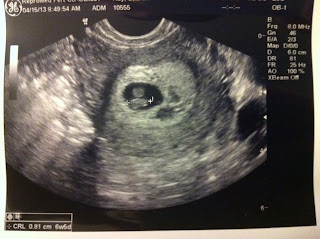

6 Week Sono

We got to see Baby again today! Its little heart was flickering away and measuring 6w5d. I was concerned about this its measurements, considering last Monday he measured 6w2d, but they told me not to worry because the early measurements are very hard to get right. After all, they are measuring something that is less than a centimeter long! I am technically 6w3d based on my last period, so it sounds like things are right on track. The bad news is my SCH has grown. They still say to just rest and take it easy. I just want this thing to go away!! I'm so grateful for where we are right now. We are on an incredible ride, and I pray every day that it continues.